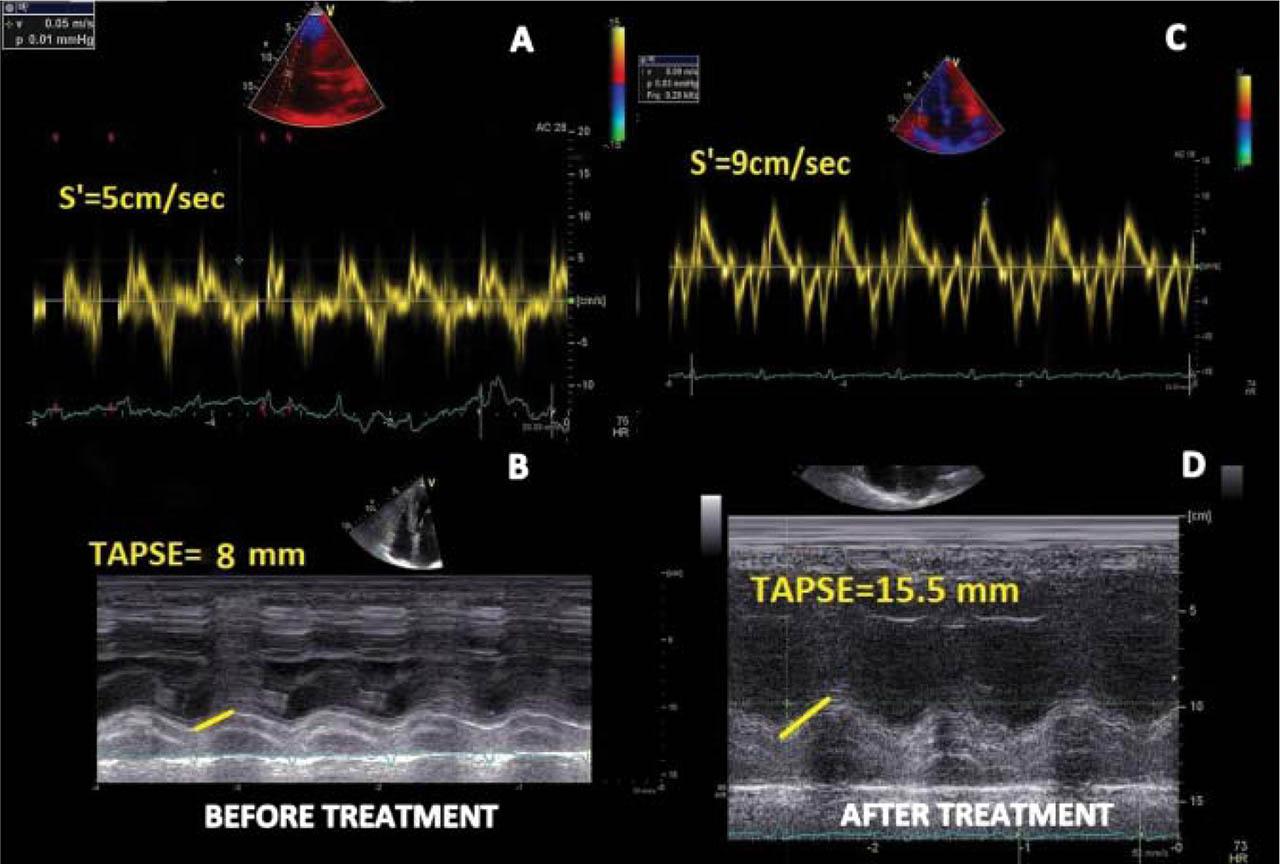

Transthoracic echocardiography (TTE) revealed nondilated LV with severe concentric hypertrophy (IVS) =17 mm, PWT =16 mm, relative wall thickness (RWT) =0.8, LV mass =157 g/m2), diffuse hypokinesia, a „ground-glass” appearance in the myocardium, and LV ejection fraction (LVEF) of 42%. A small pericardial effusion was present (Figure 2 A). Diastolic dysfunction (DD) was confirmed as grade III (E/A=3, E= 97 cm/sec, E/E’= 25) with severely biatrial dilation (LA volume = 63 ml/m2; RA volume = 54 ml/m2) and mild to moderate mitral regurgitation (Figure 2 B, C and D). The right ventricle (RV) had an increase in wall thickness (free wall = 8 mm) and severely altered systolic function (TAPSE =8 mm, S’= 5 cm/sec) (Figure 3 A and B). Severe tricuspid regurgitation with pulmonary hypertension (estimated sPAP = 46 mmHg) was also noted (Figure 4 B). 2D speckle tracking echocardiography (STE) was used to quantify myocardial deformation. Global LV longitudinal peak systolic strain (GLS) was significantly impaired (−8.4%), with a severe altered deformation in all three layers, mainly at the basal and midventricular segments and relatively preserved at the apical level, resulting in a typical apical sparing strain pattern (Figure 4A).

Figure 3

Transthoracic echocardiographic images for right ventricle before and after chemotherapy and stem cell transplantation. A and B (before treatment): altered longitudinal systolic function (TAPSE = 8 mm, S’= 5 cm/sec) at initial diagnosis; C and D (after treatment): improvement in longitudinal systolic (TAPSE = 15.5 mm, S’= 9 cm/sec) at 6 months follow up. TAPSE: tricuspid annular plane systolic excursion; s’= peak systolic velocity.

The final diagnosis was AL amyloidosis (primary amyloidosis) with cardiac involvement. Cardiac specific treatment included salt restriction, small doses of diuretics (furosemide 20 mg o.d), and mineralocorticoid receptor antagonists (spironolactone 25 mg o.d) which led to a gradually improvement of congestion. We decided to continue treatment with metoprolol succinate 25 mg o.d, perindopril 2.5 mg o.d, and atorvastatin 20 mg o.d, well tolerated. Moreover, at this stage we agreed for no anticoagulation before haematological treatment. The patient was referred to a haematological centre and specific treatment with VCD (bortezomib-cyclophosphamide-dexamethasone) was started, as well as auto-stem-cell transplantation. All treatments were well tolerated, and no major side effects were observed. At 6 months follow up, the patient reported a significant improvement in her functional capacity, exercise tolerance, and presented a significantly decrease in NTproBNP level, up to 1500 pg/mL. A follow up TTE showed improvement of the LVEF from 42% to 55%, and of the GLS form −8% to −11% (Figure 4 A and C), decrease in the left and right atrial volumes (at follow up: LA = 40 ml/m2 and RA = 30 ml/m2), and a significant regression of tricuspid regurgitation, from severe to moderate (Figure 4 B and D). Moreover, there was a significant improvement in the RV systolic function (TAPSE = 15.5 mm, S’ = 9 cm/sec) (Figure 3 C and D), with a reduction in pulmonary hypertension (sPAP = 34 mmHg). All of these findings suggested a regression of myocardial inflammatory λ light chains infiltrates as a result of chemotherapy response.